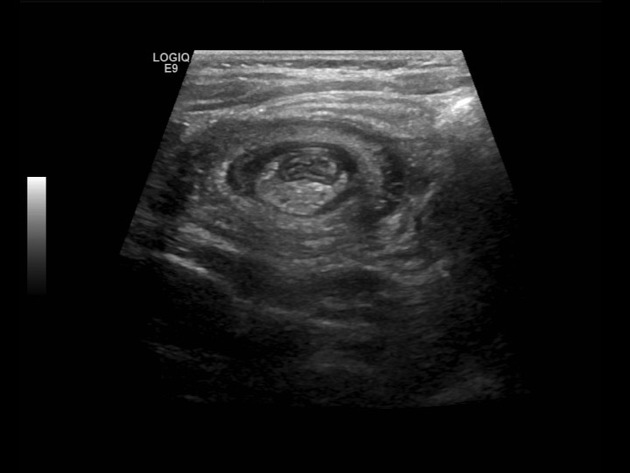

생후 4주된 남아가 식후에 자주 토하는 증상을 보인다고 어머니가 병원을 찾았다. 구토는 비담즙성으로 분출하는 양상을 보인다. 진찰 시 상복부에서 올리브와 유사한 크기의 덩어리가 촉지되었다. 혈액검사 결과와 복부 초음파 사진이다. 이 환자의 진단은 무엇인가?

• 생후 4주된 영아가 비담즙성 분출성 구토를 보이므로 비대 날문 협착증을 의심할 수 있다. 상복부의 올리브 크기 덩이가 촉지되는 것도 이를 뒷받침한다. 초음파 상 wall thickness가 증가(두께 ≥ 4mm)된 pylorus가 관찰되어 확진할 수 있다.